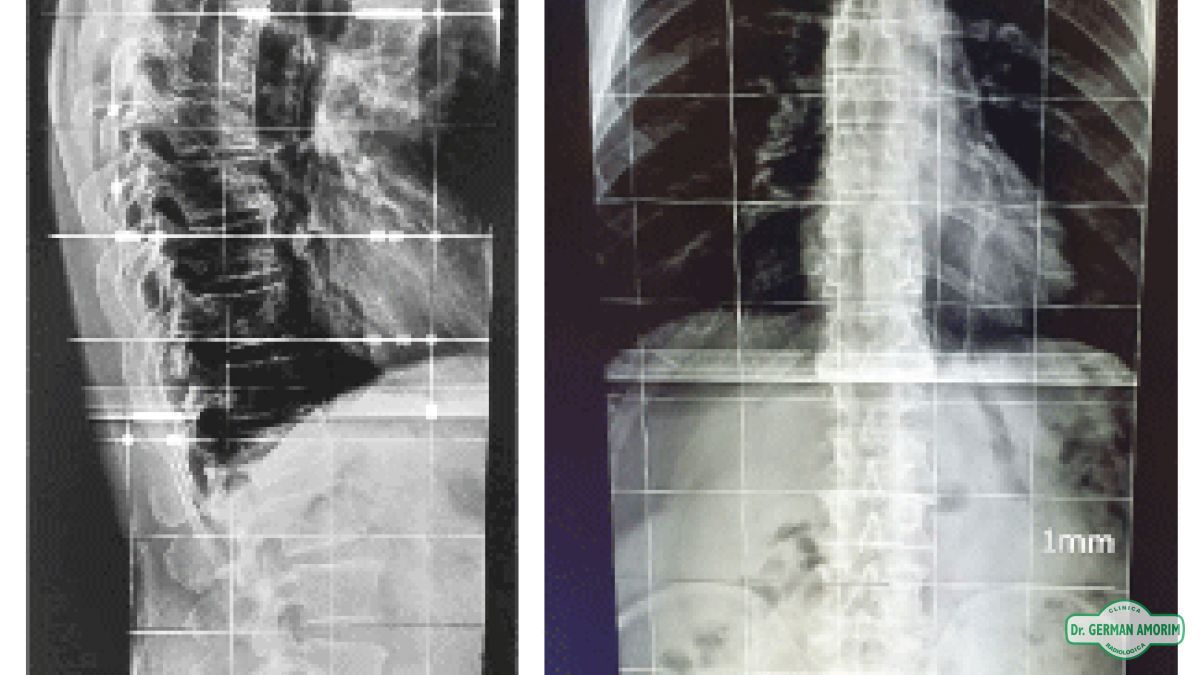

Un espinograma es una radiografía que incluye toda la columna desde el cuello hasta la pelvis en una sola placa.

El espinograma o espinografía es un estudio de rayos X que abarca toda la columna vertebral o espina (desde el cuello y hasta la pelvis).

Obteniendose así una vista panorámica de toda la columna. Se realiza en posición de frente o de perfil. Se muestra toda la imagen en una sola placa.

Actualmente se realizan espinogramas digitales que permiten de manera informática medir la alineación y los ángulos de las curvaturas de la columna tanto normales como patológicas.